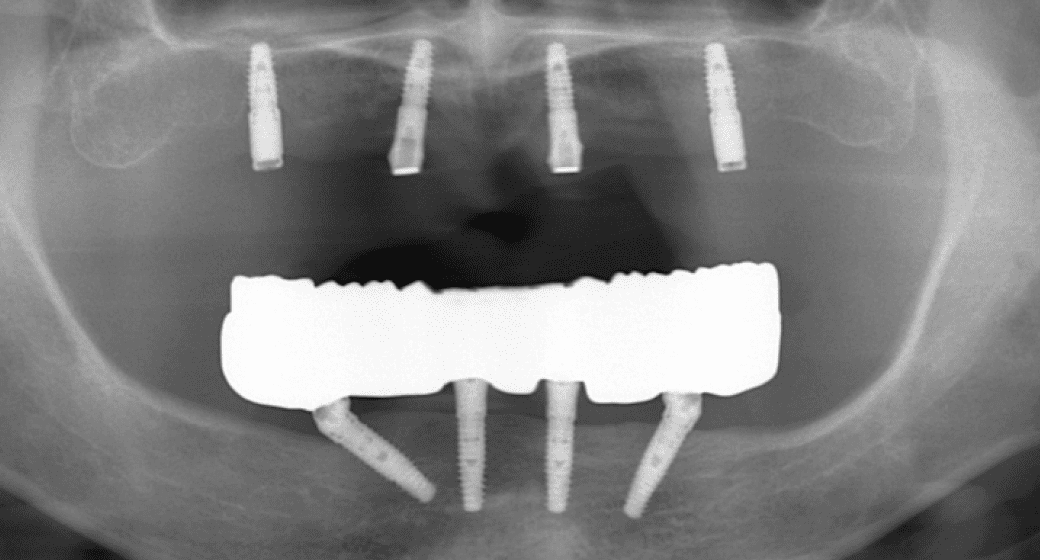

当院では、CT撮影による3D画像診断をもとに、骨の厚みや高さ、密度を立体的に把握。必要があれば、骨造成を取り入れたインプラント治療計画をご提案しています。

代表的な再生療法のひとつが「GBR(骨誘導再生法)」です。骨が不足した部位に自家骨や人工骨を補填し、特殊な膜(メンブレン)で覆うことで、骨の再生を促しインプラントの土台を築く方法です。

また、上顎奥歯など骨が特に薄い部位には「サイナスリフト(上顎洞底挙上術)」が適応されます。上顎洞と呼ばれる空洞の底を持ち上げ、その下に骨を造成することで、十分なインプラント埋入スペースを確保することが可能になります。

これらの高度な再生治療は、歯科用CTや精密シミュレーション技術、そして確かな経験を持つ術者による対応が前提となります。